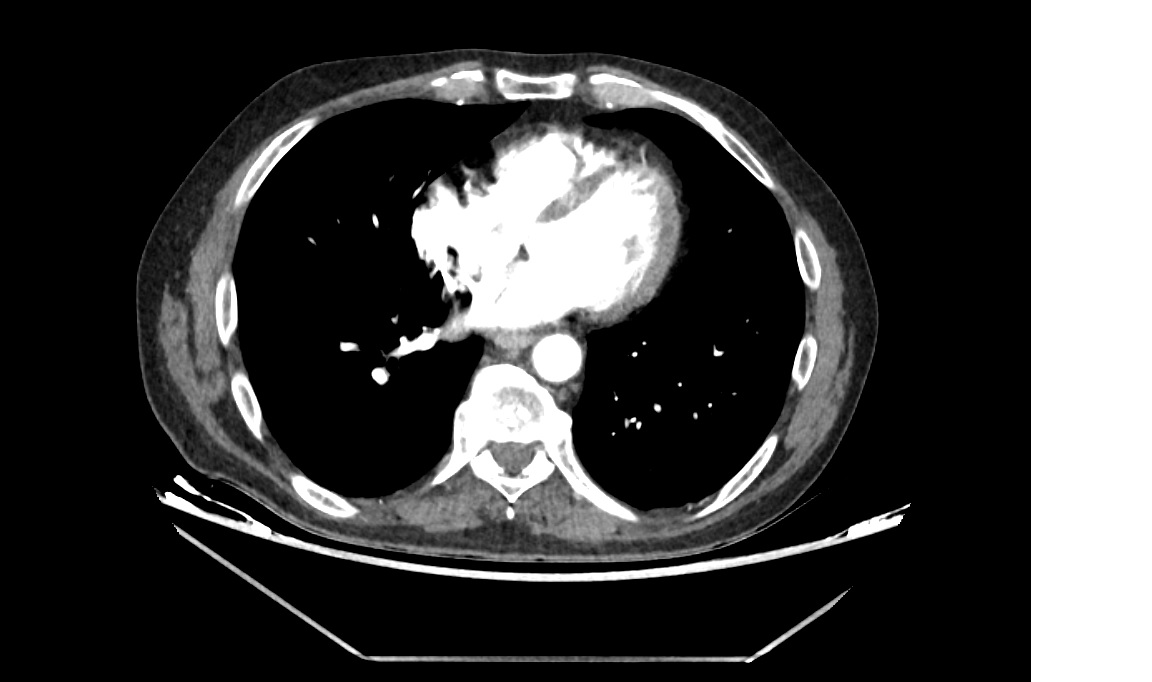

En el hospital se realiza TAC abdominopélvico observándose: signos de cistoprostatitis con abceso de 15 mm y hallazgo incidental de aneurisma de aorta abdominal infrarrenal (3,8x3,6 cm) con signos de rotura contenida y trombo mural excéntrico.

Hallazgo incidental de aneurisma aórtico abdominal con rotura contenida, planteando el dilema clínico entre infección activa y cirugía urgente. Problemas identificados: infección urinaria por E. coli y riesgo vital por aneurisma roto contenido.